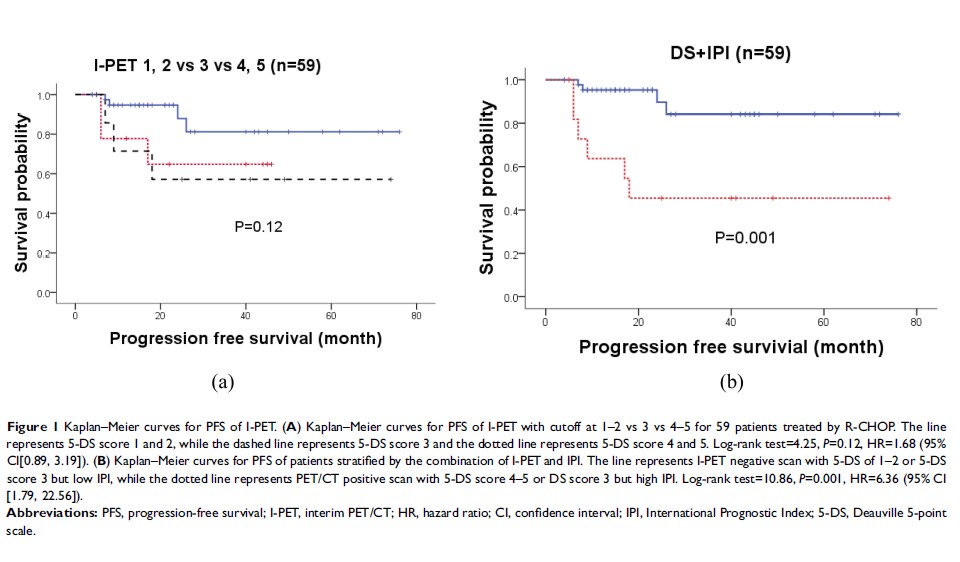

Original Research

结合中期 PET/CT 多维尔评分和国际预后指数对弥漫大 B 细胞淋巴瘤患者的预后风险分层

- 作者:孙红卫,余湛,马宁,周洁,田蓉蓉,赵铭,王彤

- 期刊:Cancer Management and Research